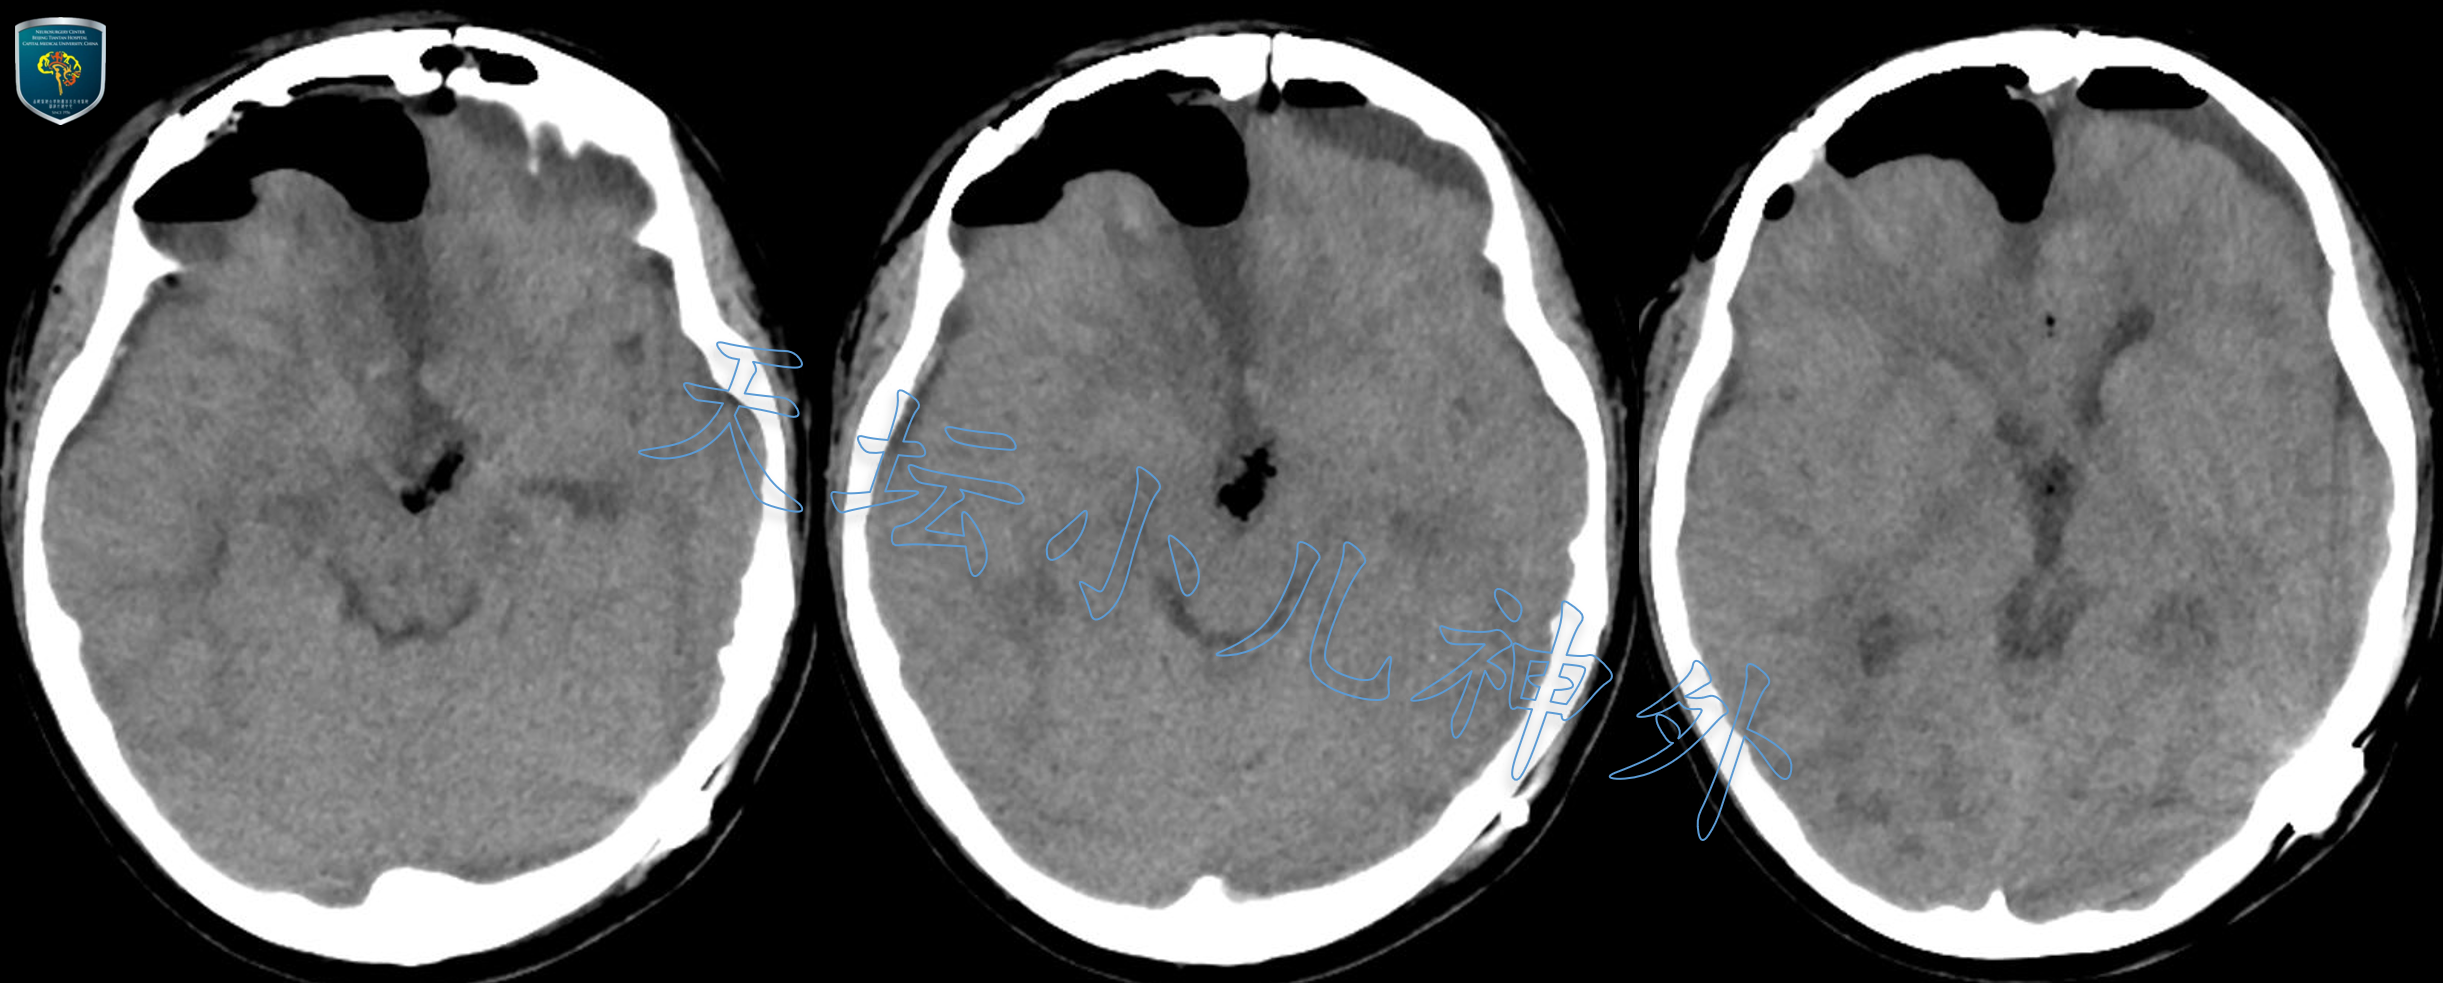

2020年8月接诊一例来自河北省唐山的12岁男性患儿(165cm,56kg)。患者主诉:间断性头痛伴呕吐3天,加重1天。查体示:生长发育基本正常;血清学提示肿瘤标记物阴性;激素水平基本正常;头颅CT/MRI示:鞍内、鞍上、三脑室区、鞍背后方巨大占位;颅咽管瘤可能性大。该病例系鞍区实体性肿瘤,非典型囊性瘤体伴蛋壳样钙化,需与视路胶质瘤、鞍区生殖类肿瘤相鉴别。鉴于首发症状无尿崩表现,肿瘤标记物阴性,MRIT1像出现脂类信号,基本除外生殖类肿瘤;患儿首发症状与视力无关,查体无水平眼震,MRI呈含脂类的混杂信号,视路胶质瘤可能性小。初步诊断为颅咽管瘤,且由于实体为主,难以植入Ommaya囊穿刺放液,只能考虑直接手术切除。

图2.术前CT见鞍区占位,实体为主,内含团块状钙化,充满脚间池并突入第三脑室。